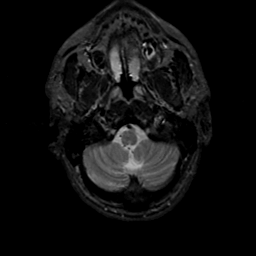

MR Study #17, July 7, 1991 -- Slice #5